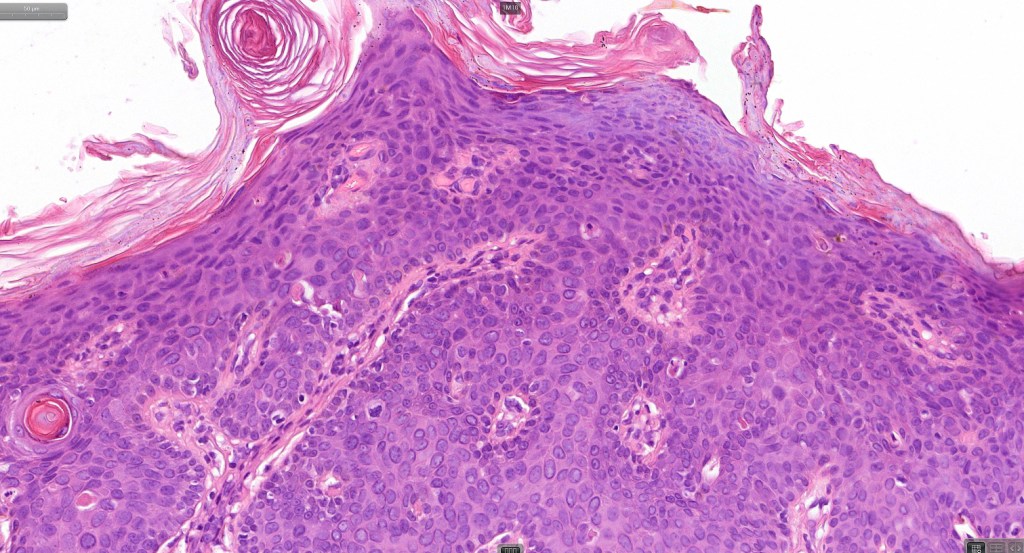

•Hyperkeratosis, parakeratosis & acanthosis

•Full thickness dysplasia (carcinoma in situ) involving the epidermis and intraepidermal adnexal elements

•Loss of maturation, nuclear pleomorphism, marked mitotic activity +/- abnormal forms

•Nested (clonal, Borst-Jadassohn) variant